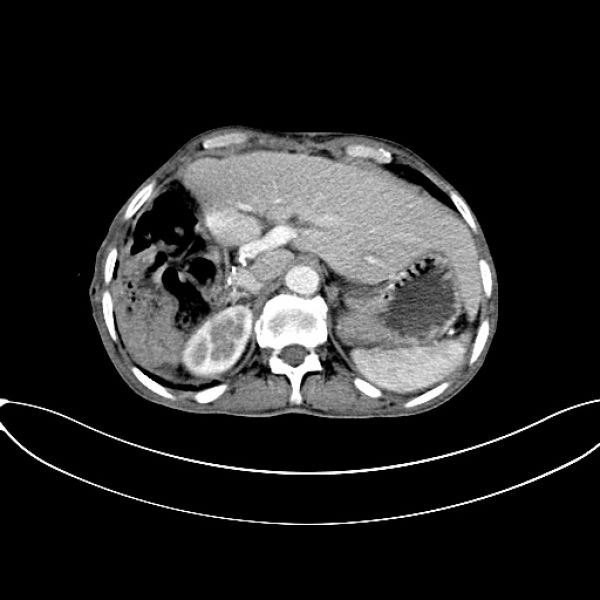

术前CT,右肝巨大肿瘤,占据右肝大部分,伴有腹腔,肝周大量积血